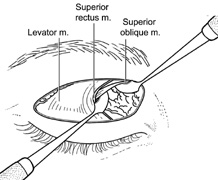

Fig. 14. A,B. Large intraorbital lymphangioma causing proptosis and optic nerve compression

in a 2-year-old child. C. View of the left orbit from above after removal of the frontal bone flap, including

the supraorbital rim and orbital roof. An extensive exposure

of the entire superior and lateral orbit is afforded. The levator

and superior rectus complex is being retracted laterally with a muscle

hook, whereas the Freer elevator retracts the superior oblique muscle

medially. The frontal nerve can be seen running from posterior to anterior

over the superior orbit. The orbital mass is exposed in this fashion. D. The fronto-orbital bone flap is wired back in place after completion of

the procedure. E. Postoperative appearance of the patient. F. The postoperative CT scan shows complete removal of the lymphangioma. This

large and diffuse lesion would have been difficult to remove with